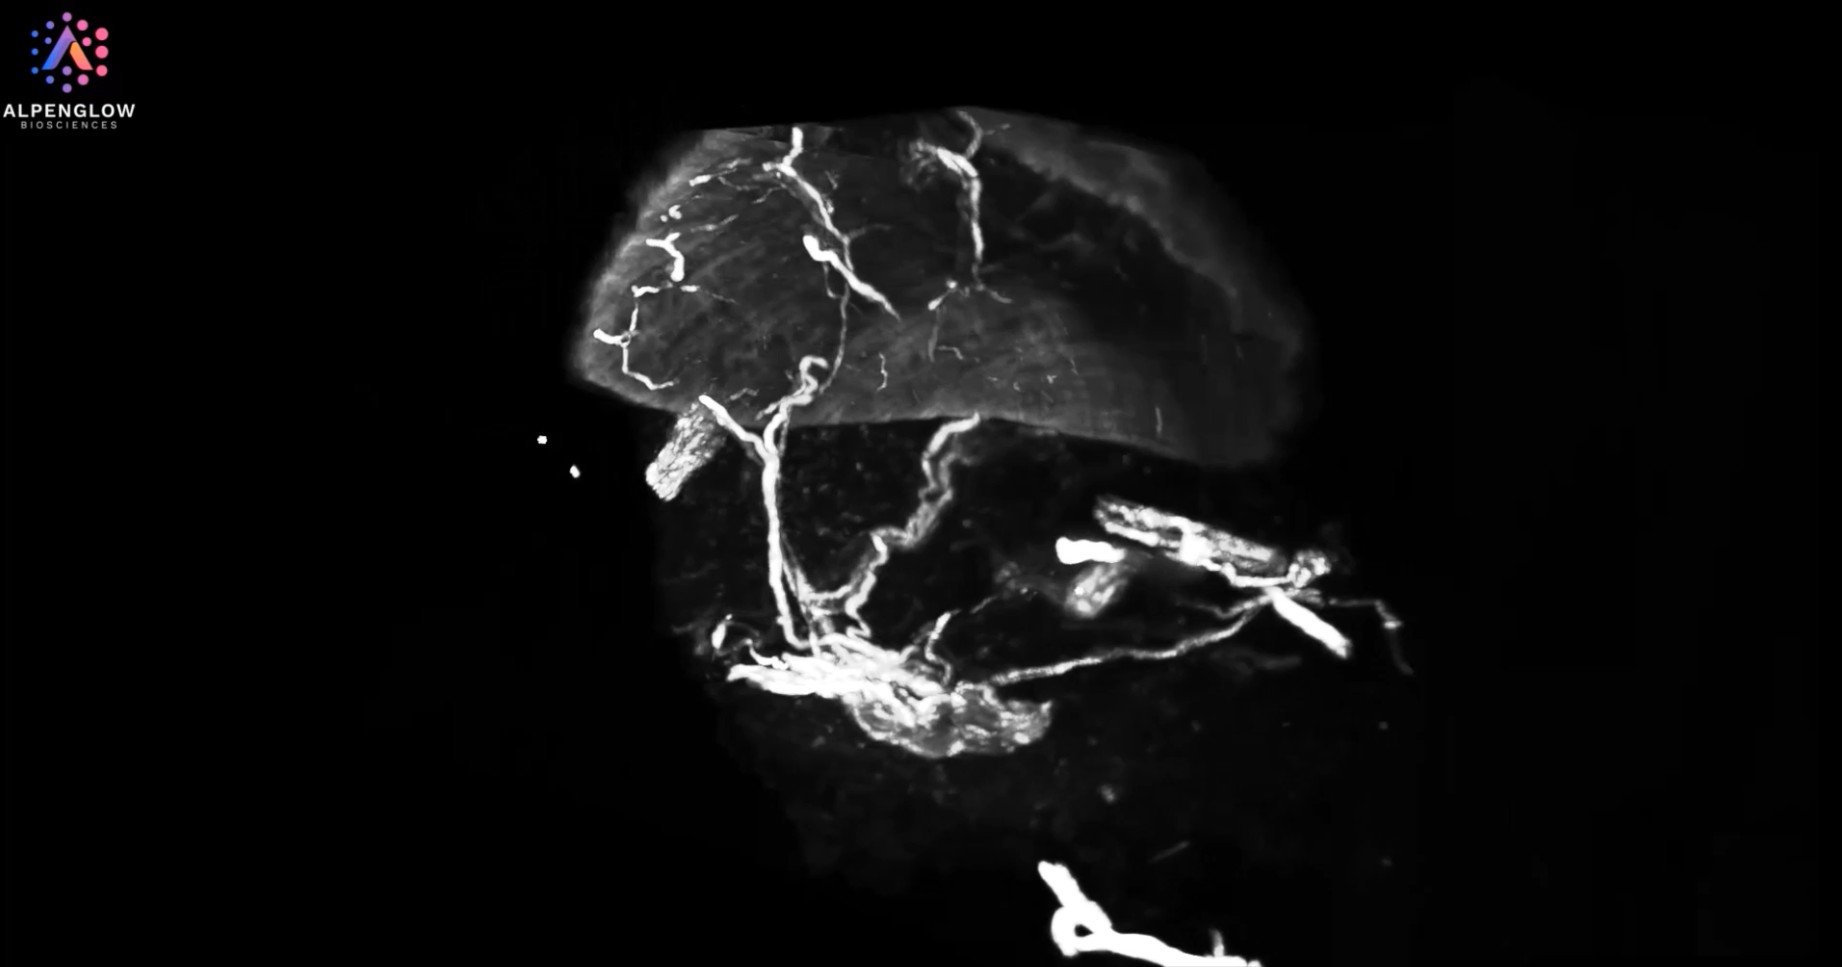

Skin biopsy in 3D: from low to high resolution

Journey through the delicate nerve structures of the epidermis and dermis at low resolution, and zoom in for an awe-inspiring close-up of lymphocyte distribution around these dynamic networks. This visualization not only captures the stunning complexity of skin biology but also delivers actionable insights, propelling advancements in dermatology research.